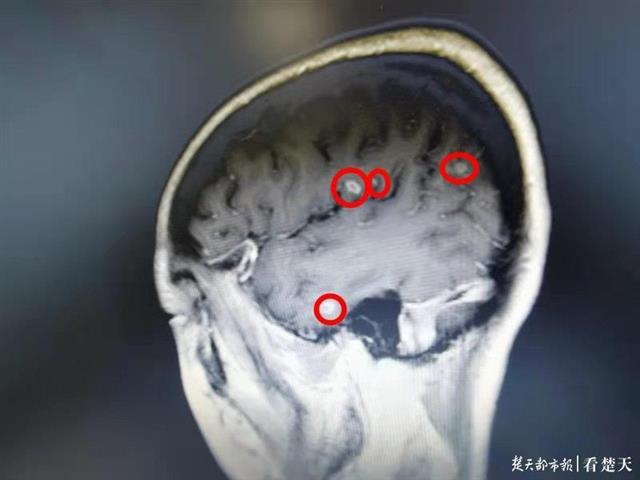

负责给小丽治疗的医生刘修平介绍,小丽颅内结核病情较重,CT可见明显病灶。耳鸣与听神经遭受结核杆菌侵扰有关。所以,无论吃多少猪耳朵,都不可能治好耳鸣,只能耽误治疗时机。